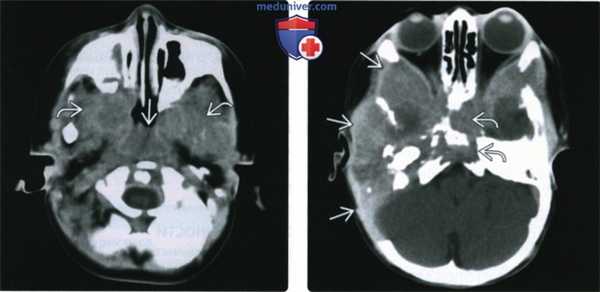

(Слева) При аксиальной КТ в костном окне определяется четко очерченный литический очаг деструкции в левой височной кости, обусловленный ЛКГ, с поражением слуховой капсулы (которая редко подвергается эрозии в большинстве ситуаций).

(Справа) При аксиальной МРТ Т1 С+ FS определяется распространенное контрастирование левой височной кости вследствие поражения ЛКГ с вовлечением окружающих экстракраниальных мягких тканей. Обратите внимание на «запертую» жидкость в задних отделах сосцевидного отростка.

(Слева) При КТ с КУ в аксиальной проекции определяется обширное поражение с выраженными изменениями мягких тканей (ЛКГ). Патологический процесс распространяется в носоглотку, а также в правое и левое носоглоточные жевательные пространства.

(Справа) При КТ с КУ в аксиальной проекции (срез проходит выше предыдущего) определяется крупное, относительно гомогенно контрастируемое объемное образование центральной части основания черепа и височной кости (ЛКГ). Объемное образование вызвало обширную деструкцию правой височной кости, крыла клиновидной кости и ската затылочной кости.